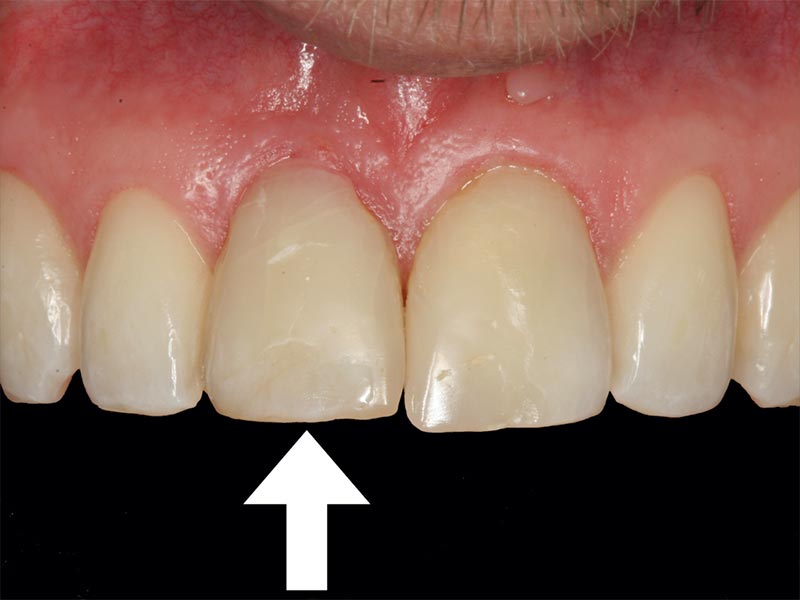

Unter dentalen Implantaten versteht man im allgemeinen eine Schraube, die dort, wo ein oder mehrere Zähne verloren gegangen sind, in den Kieferknochen "eingepflanzt" wird. Diese Therapieform der Implantologie hat sich in den letzten Jahren zu einem alltäglichen Therapieverfahren in der Zahnheilkunde entwickelt. Wissenschaftliche Untersuchungen zeigen hierfür eine Erfolgsquote von i. d. R. 80-98 % über 10 Jahre. Verglichen mit anderen zahnärztlichen Maßnahmen gibt es nahezu keine andere Therapie mit derart guten Erfolgsaussichten. Auch eine Verbesserung der Lebensqualität wird durch implantatgetragenen Zahnersatz laut klinischer Studien erreicht.

Mittlerweile hat sich die Implantologie zu einem alltäglichen Therapieverfahren mit sehr guten Erfolgsaussichten in der Zahnheilkunde entwickelt. Bei guter Mundhygiene und regelmäßigen Kontrolluntersuchungen können fachmännisch gesetzte Zahnimplantate ein Leben lang halten.